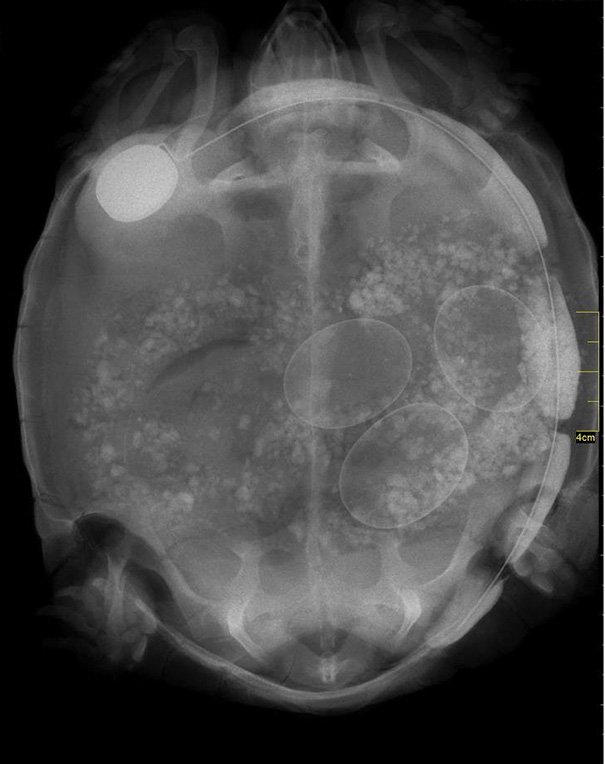

черепаха